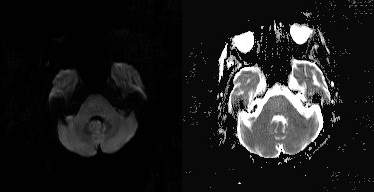

(3)EPM,病灶多对称位于基底核团或丘脑,少数病例可累及皮层,信号表现与 CPM 相似,但病灶形态不相同

对称性壳核受累,桥脑未见病灶

对称性壳核和尾状核受累,扩散受限